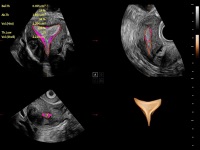

豐富的血流動(dòng)力學(xué)檢測(cè)技術(shù),可在不同醫(yī)療場(chǎng)景中高效捕捉血流信號(hào),助力臨床診療。

在傳統(tǒng)血流的基礎(chǔ)上優(yōu)化掃查和算法策略,能夠更好的抑制組織信息,提煉紅細(xì)胞運(yùn)動(dòng)信息,得到更高幀頻,高靈敏度和分辨率的血流信號(hào),還原更真實(shí)的血流動(dòng)力學(xué)。

通過光照模型,使二維血流顯示出立體的效果,增加血流的敏感性、成束性,減少外溢??梢院推渌煌难骷夹g(shù)聯(lián)合使用,融合不同技術(shù)的優(yōu)勢(shì)。輕松應(yīng)對(duì)微小血管,增強(qiáng)血流的立體效果,提升視覺敏感性。

通過創(chuàng)新的Matrix E自適應(yīng)濾波算法,能有效濾除軟組織和噪聲信號(hào),最大限度保留超低速微細(xì)血流的信號(hào);結(jié)合超長時(shí)間域算法,極大提升細(xì)微血流的敏感性和空間分辨率,更真實(shí)的反應(yīng)組織、包塊的血流灌注情況。